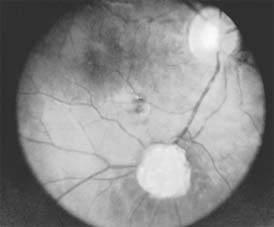

Figure 10-31

Figure 10-31: Retinal astrocytic hamartoma.